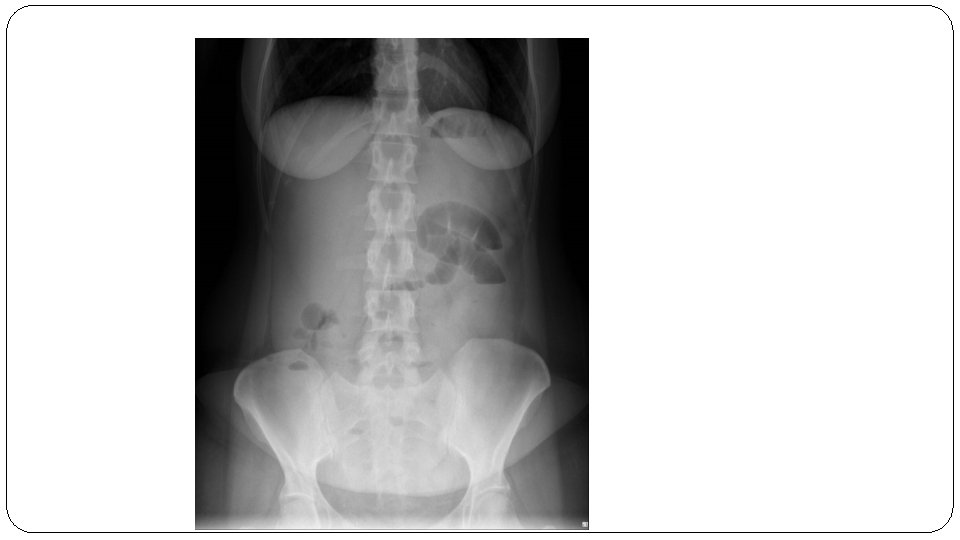

Normal abdominal X-ray

Location Small bowel Large bowel Central Peripheral Wall Pattern Encircling valvulae conniventes visible depending on degree of air filling/distention. Haustral folds interspaced with Plicae semilunaris Size 6 cm diameter (caecum 9 cm) 3 cm diameter